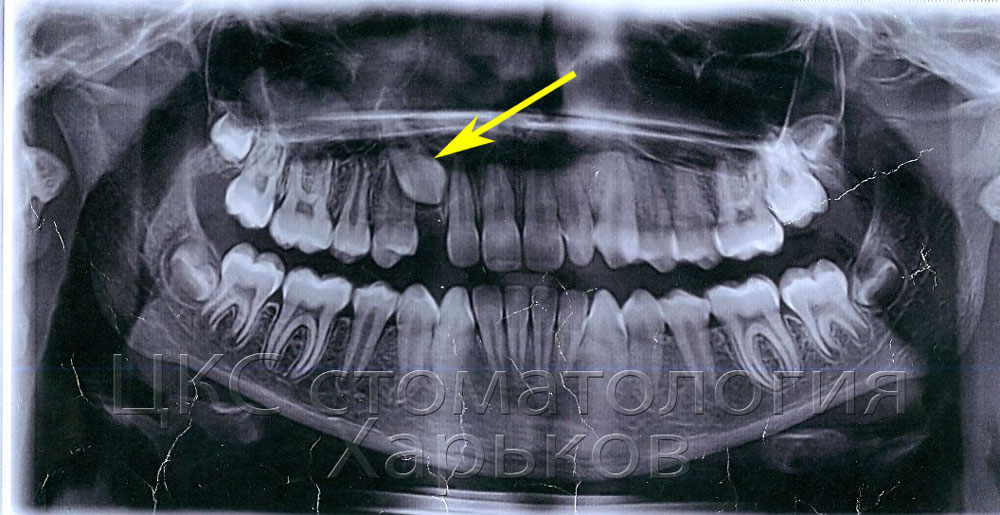

Удаление молочного зуба.

Удаление зуба